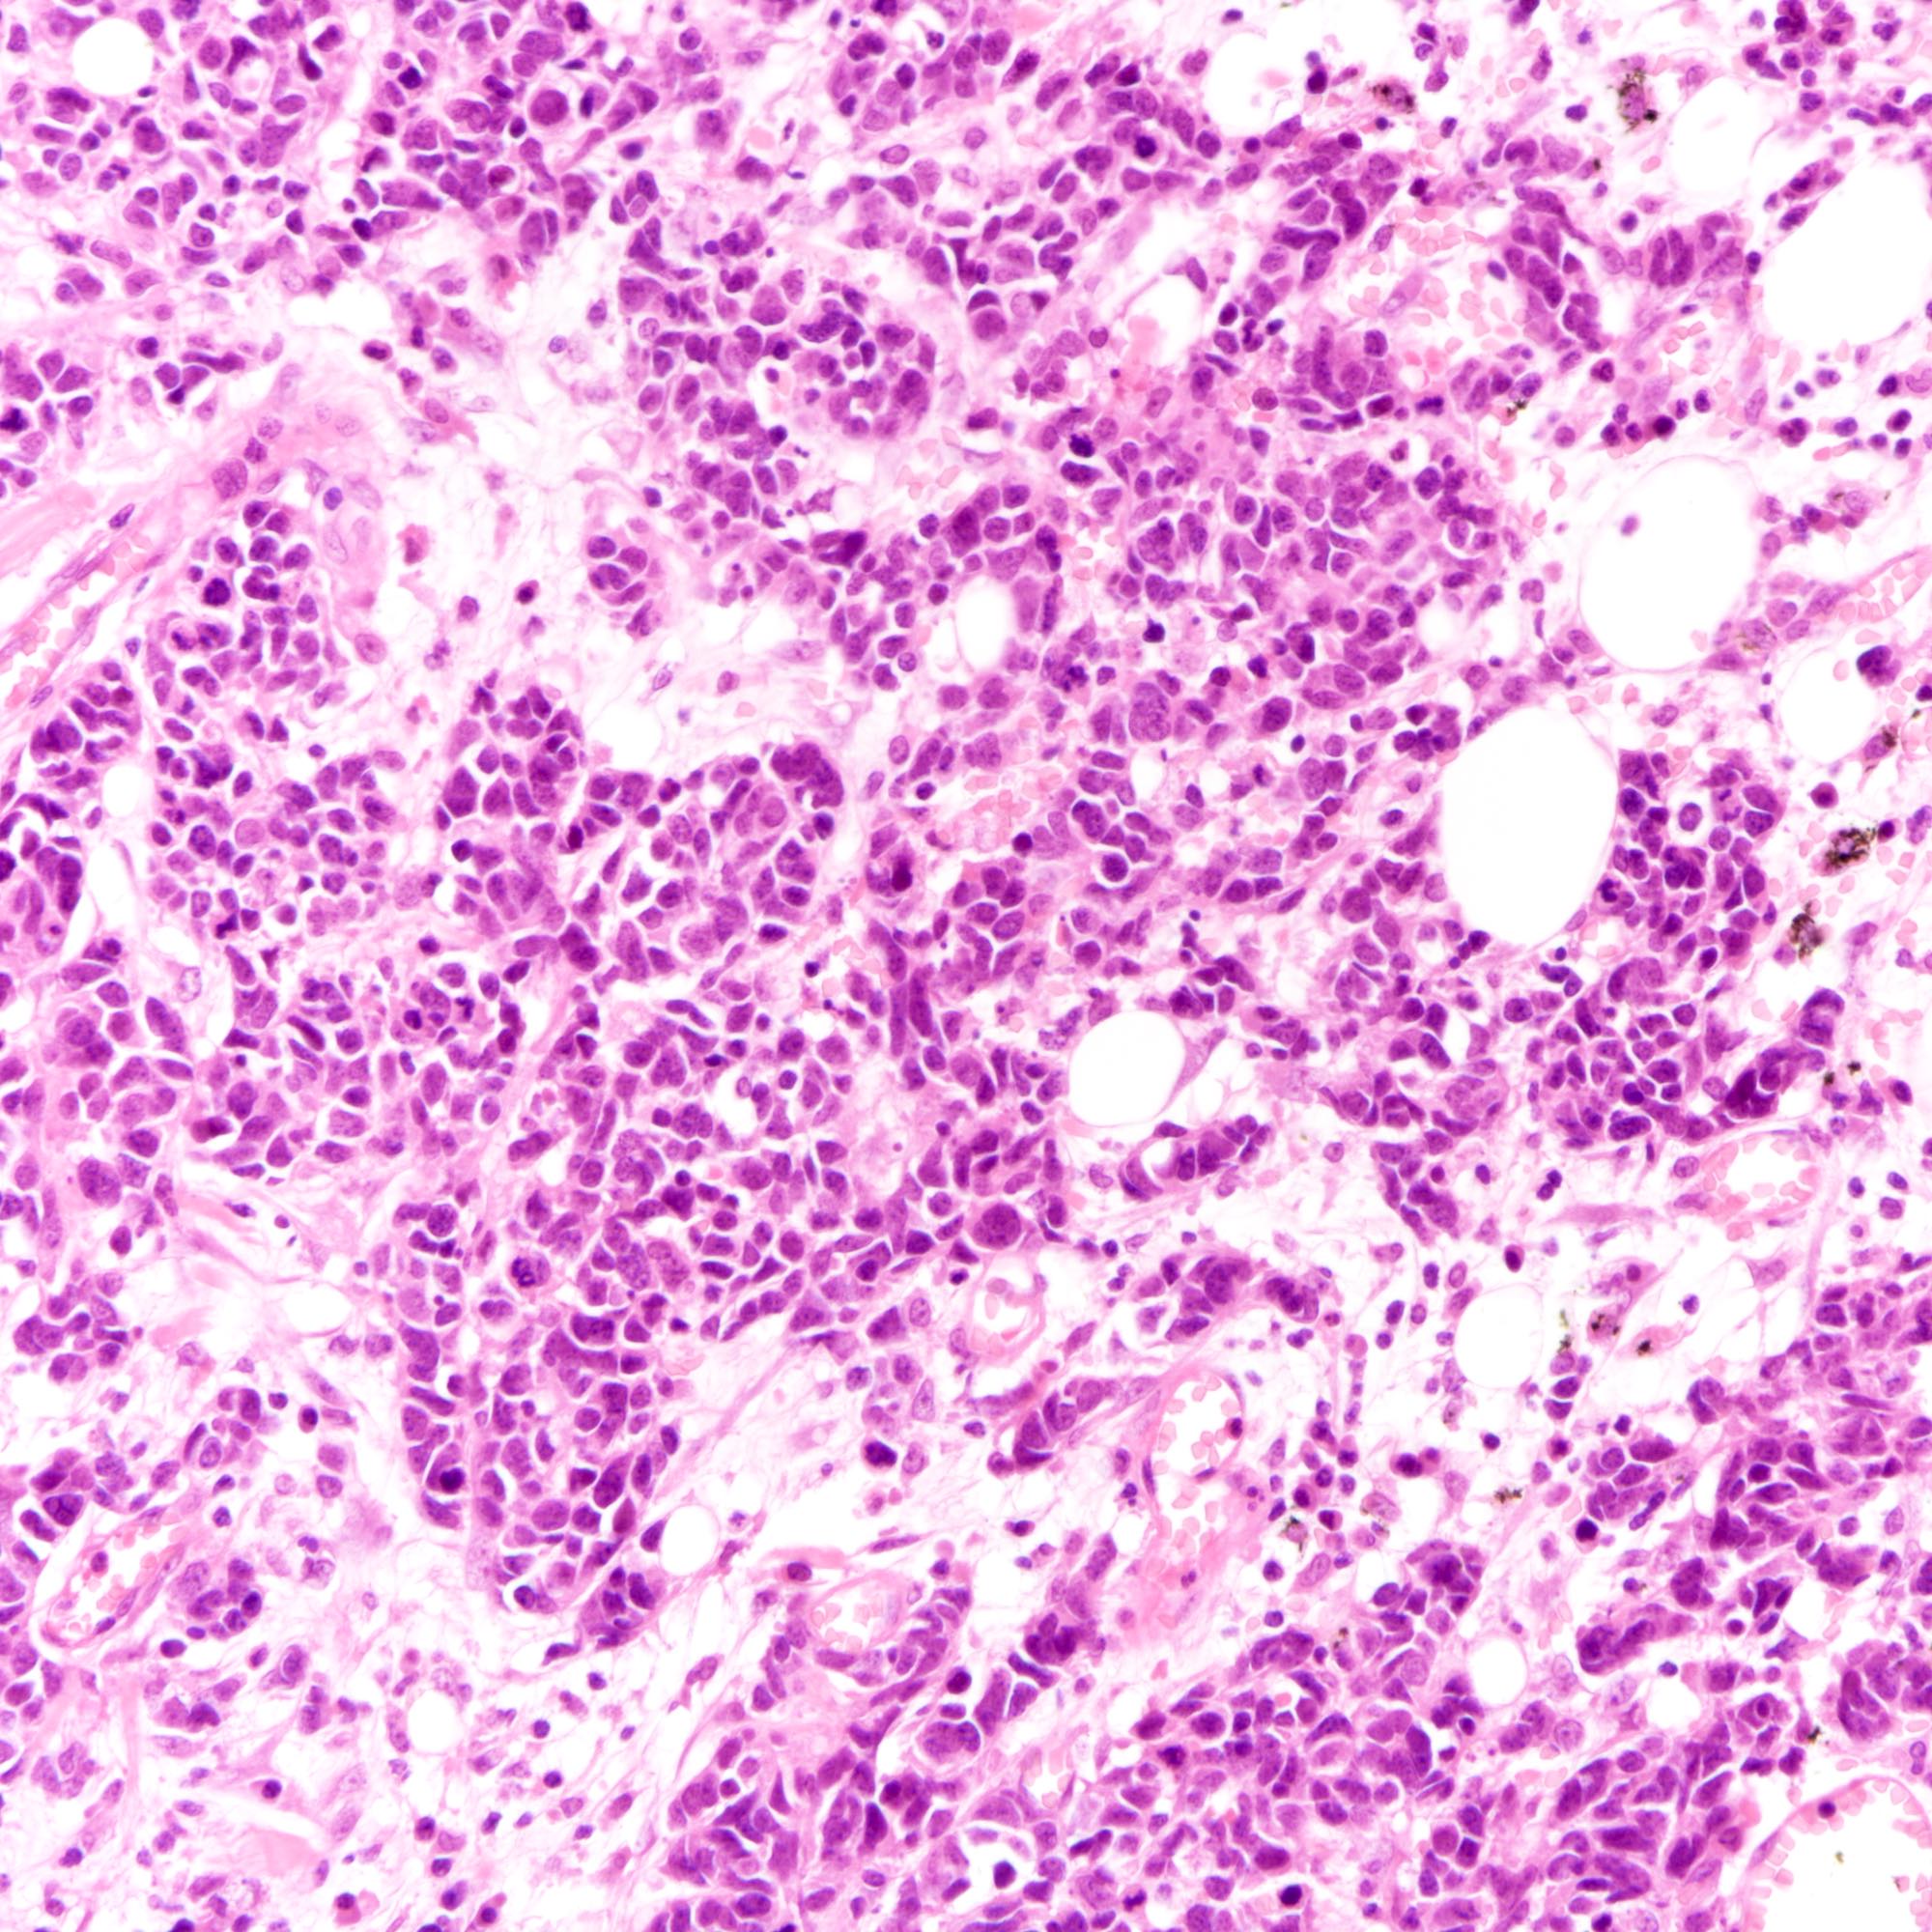

Microscopic (histologic) images

Contributed by Joshua J.X. Li, M.B.Ch.B., Gary M. Tse, M.B.B.S. and Kristen E. Muller D.O.

Large cell carcinoma

- Small cell carcinoma:

- Infiltrative growth pattern

- Crush artifact frequent

- Necrosis and lymphovascular invasion common

- Tumor cells densely packed with ill defined cell borders

- High N/C ratio with scanty cytoplasm

- Small dark hyperchromatic nuclei and inconspicuous nucleoli

- Mitotic count high

- Large cell carcinoma:

- High grade features (frequent necrosis, lymphovascular invasion and mitosis) similar to small cell carcinoma

- Tumor cells have a larger amount of cytoplasm

- Chromatin pattern coarse with occasional distinct nucleoli

- Neuroendocrine carcinomas of the breast histologically indistinguishable from their counterparts of other primaries